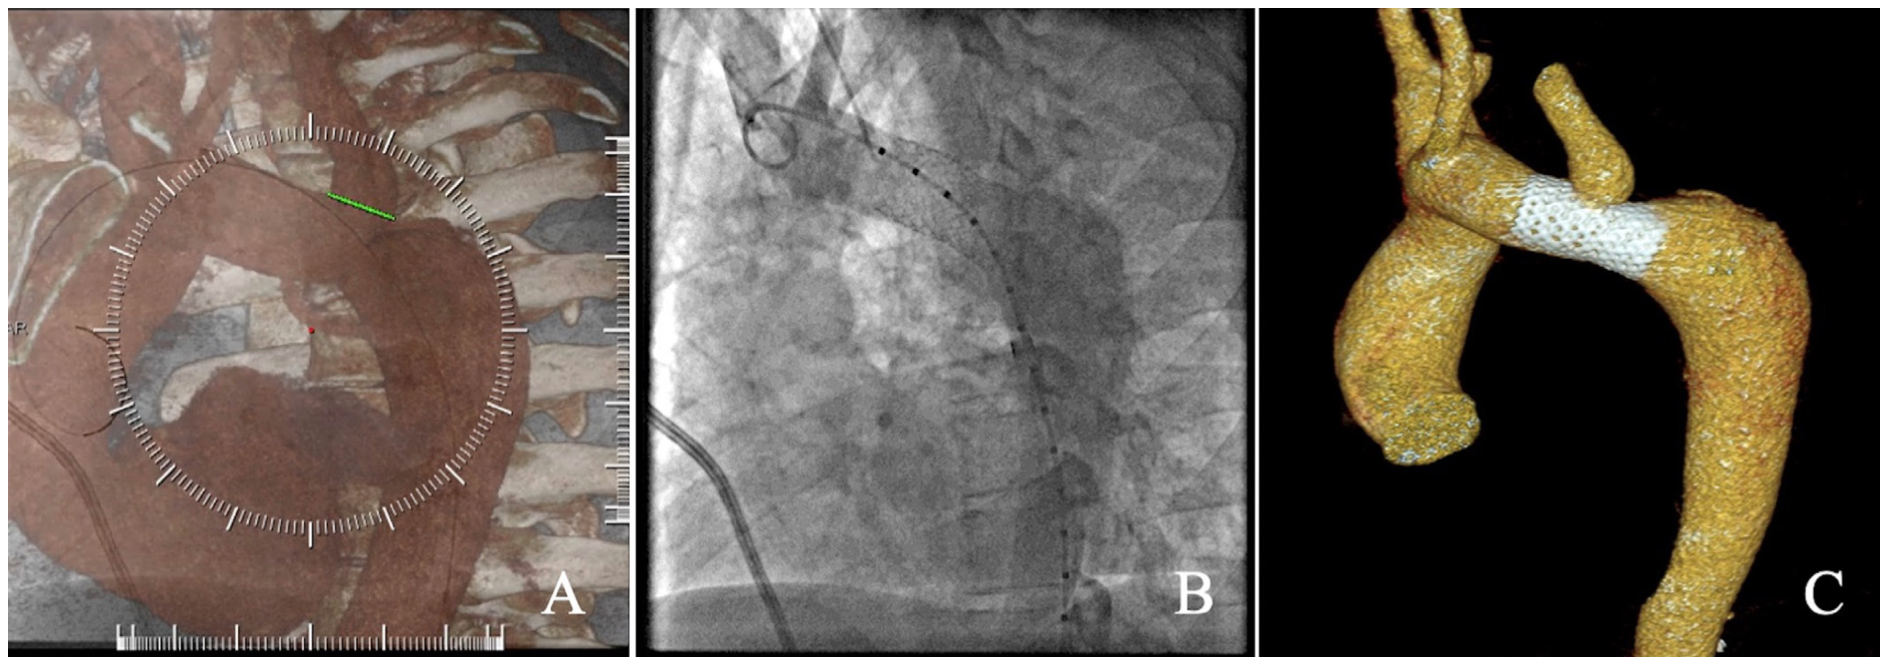

Coarctation stenting procedure. The procedures took place in the catheterization laboratory, where access was obtained in the right femoral artery and vein and the right radial artery. Right and left heart catheterization were performed in order to obtain baseline TSG, followed by aortography. Invasive measurement of the left subclavian artery pressure while ballooning its origin was done in select cases in which the subclavian artery might have been covered by a stent. Standard and rotational angiography with fusion imaging (2D-3D/3D-3D overlay) or cone-beam CT with fusion imaging was performed in order to mark important anatomic landmarks, such as the left subclavian origin, point of maximum narrowing, and length of the affected segment. TEVAR was performed with a bare or covered balloon-expandable stent mount on a balloon-in-balloon (BIB) catheter (NuMed). Rapid ventricular pacing was used in short or technically difficult proximal landing zones. Postprocedural TSG was measured; if not satisfactory, additional ballooning or stenting was performed. Final angiographies were obtained and the femoral vascular accesses were percutaneously closed (Figure 1).